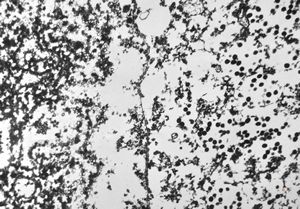

M,50y. | Pneumocystis carinii - lung